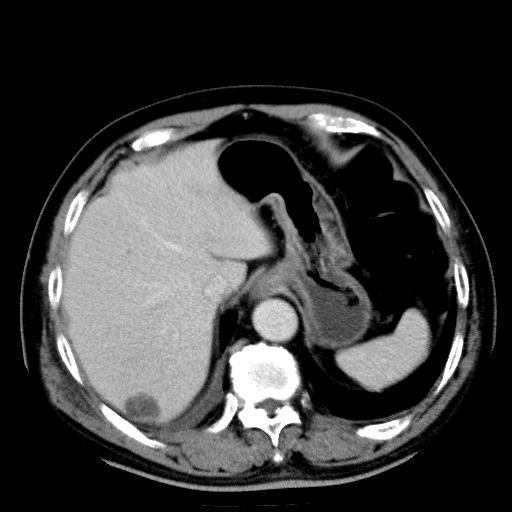

以下是引用zhctwbh在2008-8-23 14:20:00的发言:[br]囊肿合并出血

以下是引用zjb在2008-8-23 16:41:00的发言:[br]囊肿并出血可能性大。